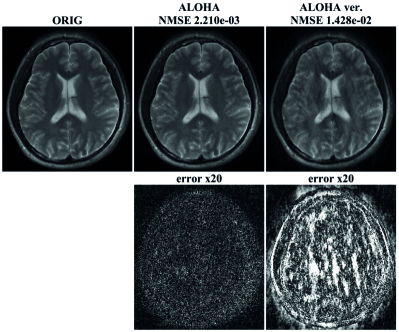

Refer to caption

Figure 3: Comparison with l1subscript𝑙1l_{1}-wavelet compressed sensing, TV compressed sensing, LORAKS, and the proposed method at four fold acceleration factors. The data was acquired from a single channel coil. The first row shows reconstructed images, and the second row shows difference images between the ground-truth and the reconstructions, and the third row shows the magnified views of distorted regions in the reconstructed images. The last row shows the difference images in the magnified views.

Reconstructed results from a single coil brain data are shown in Fig. 3 with the NMSE values. From the NMSE values, we observed that the performance ALOHA was quantitatively superior to the performance of l1subscript𝑙1l_{1}-wavelet and TV based compressed sensing approach. The reconstruction results by ALOHA has less perceivable distortion compared to those of l1subscript𝑙1l_{1}-wavelet and TV approaches. This can be easily observed from the difference images in the second and the fourth rows of Fig. 3. In the case of l1subscript𝑙1l_{1}-wavelets and TV, structural distortion around the image edges was easily recognizable. In the last row of Fig. 3, the edges were reconstructed accurately by ALOHA. On the other hand, the contrast between grey matters and white matters in l1subscript𝑙1l_{1}-wavelets and TV reconstruction were significantly distorted compared with that of ALOHA. The LORAKS reconstruction appeared better than that of l1subscript𝑙1l_{1}-wavelets and TV reconstruction, but there were still remaining errors around the edges and the NMSE value was much higher than that of ALOHA.